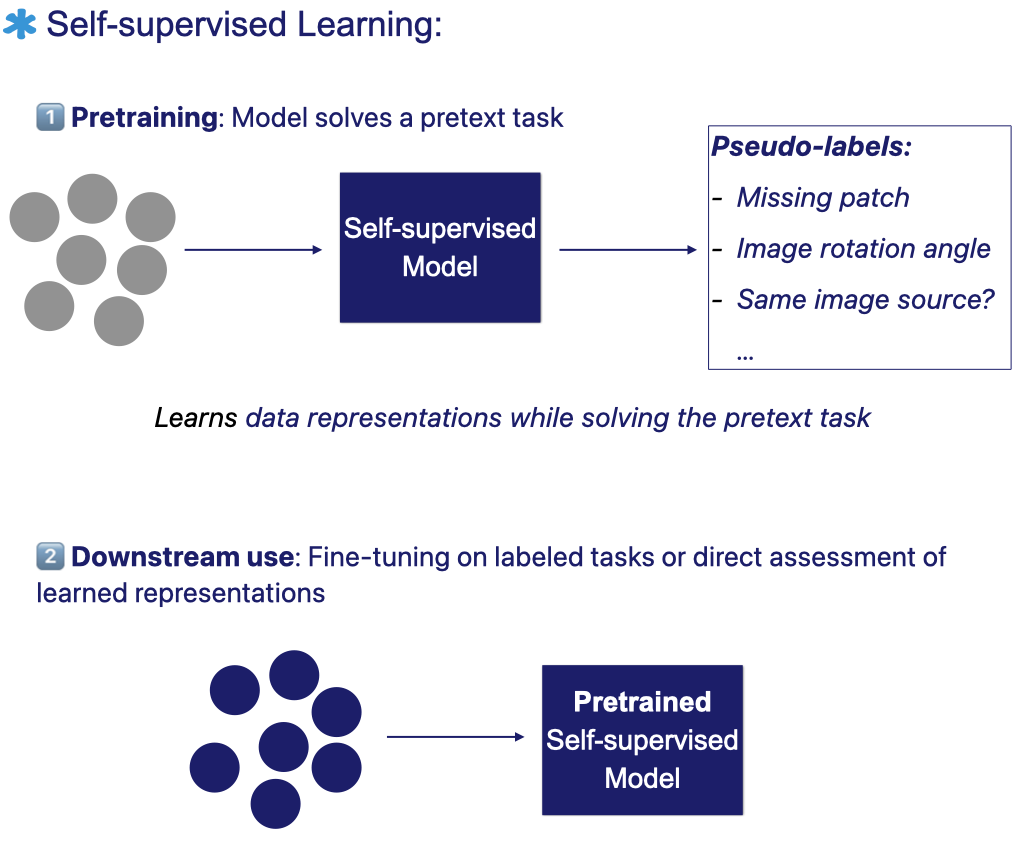

Self-supervised learning (SSL), a branch of unsupervised learning, aims to extract meaningful and discriminative representations directly from unlabeled data, without requiring human annotations [11].

In SSL, the model learns by solving a pretext task that it generates from the data itself – for example, predicting a missing patch, estimating an image’s rotation, or determining whether two views originate from the same source.

A typical SSL workflow involves two stages:

- Pretraining: the model solves a designed pretext task, where pseudo-labels are automatically generated from the data’s own structure and attributes.

- Fine-tuning or direct assessment: after pretraining, the model can either be fine-tuned on a labeled downstream task or directly evaluated to assess the quality of its learned representations [11].

Many studies have found that models perform better on downstream tasks when their feature extractors start from self-supervised pretrained weights rather than being trained from scratch with random initialization [12].

Pretraining generally helps models learn more efficiently, whether it’s used as an initial step with all labeled data or, more importantly, when labeled samples are scarce.

The figure below illustrates the self-supervised learning workflow: the model first learns from unlabeled data through a pretext task with automatically generated pseudo-labels. It then transfers the learned representations to downstream tasks using labeled data.